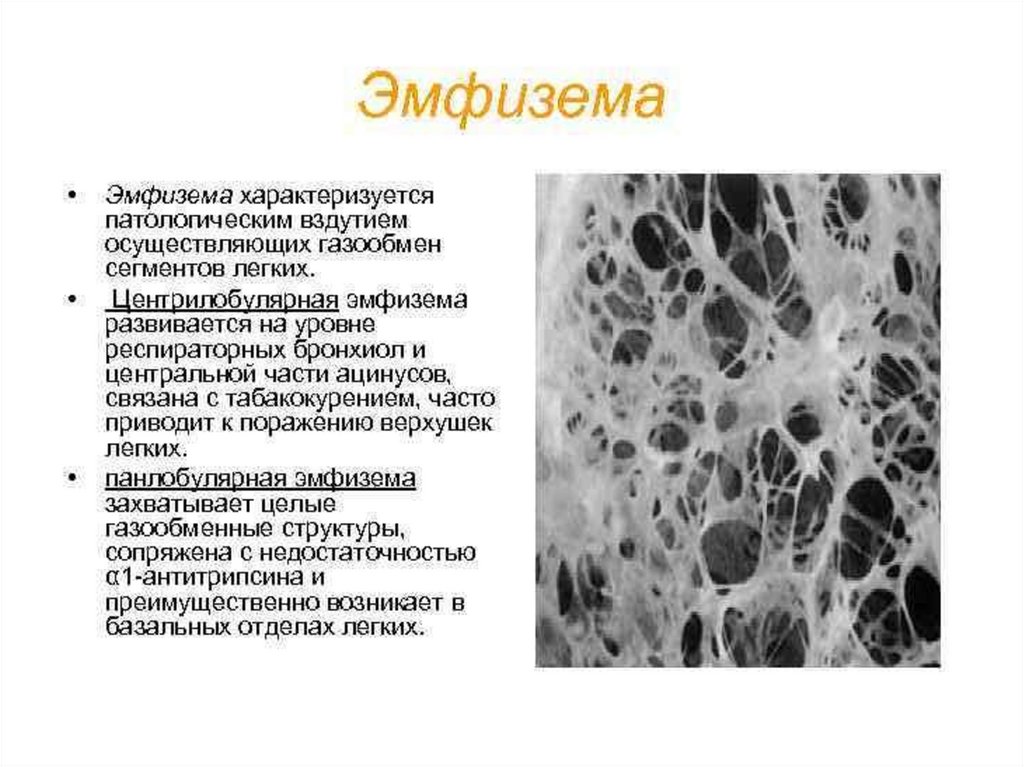

Эмфизема легких

Эмфизема легких.